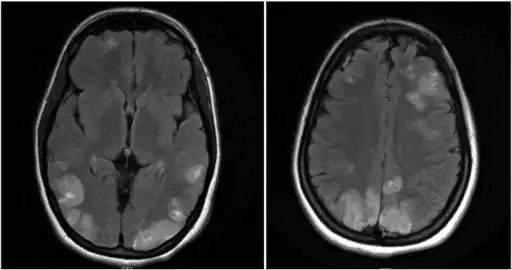

Image shows faint multifocal and bilateral hyperintensities in the frontal lobes and parietooccipital lobes, extending to the left greater than right posterior temporal regions -